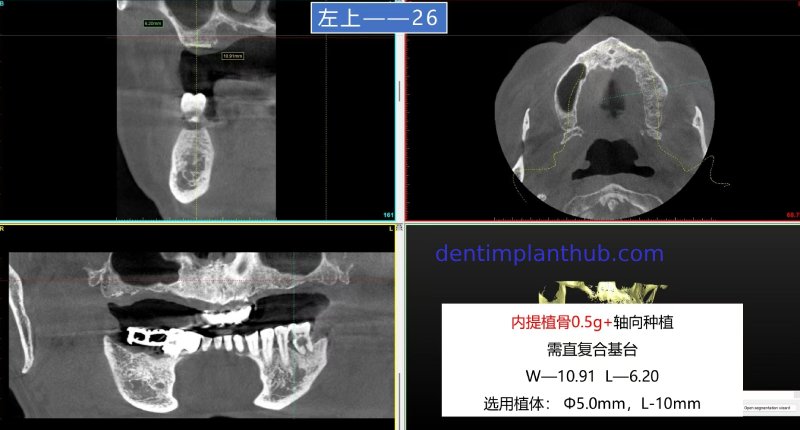

For tooth 26, with a width of 10.91 and a height of 6.20, an implant with a diameter of 5 and a length of 10 is selected. It will be implanted axially. An internal maxillary sinus lift is required, with 0.5 grams of bone graft material to be implanted, and a straight composite abutment is needed.